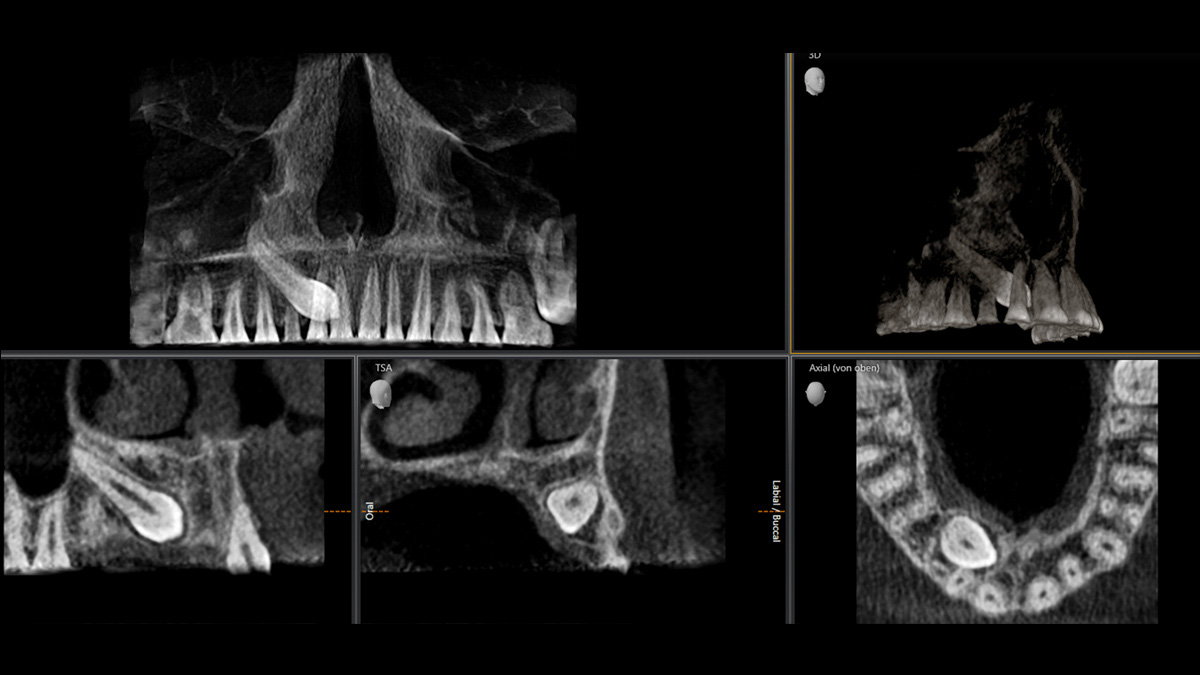

With the 3D Intelligent Low Dose mode, you get 3D images in the dose range of a 2D X-ray. In HD mode (up to 1,400) individual images are captured during a single rotation and converted into a 3D volume with up to 80 μm for low-noise images in high resolution.

A broad range of volume sizes to support your various diagnostic and clinical needs from Ø 5 x 5.5 cm to Ø 11 x 10 cm